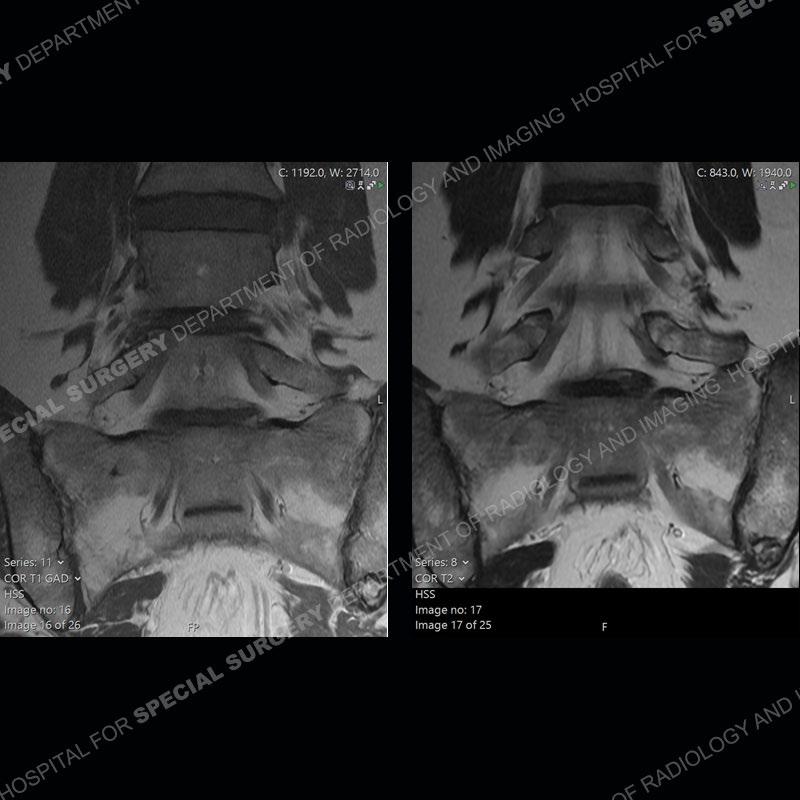

Post operative changes are seen on the left side at L5-S1 where there is near complete removal of the left sided L5 lamina, partial resection of the left L5-S1 facet joint, and resection of the left sided ligamentum flavum. In the anterolateral epidural space about the subarticular recess is a mass that demonstrates similar T1 and T2 signal characteristics to the adjacent degenerated disc. There is enhancement about the periphery of the mass, but the majority of this somewhat geographic or polyploid mass demonstrates no enhancement. The mass exerts prominent mass effect on the left S1 axillary sleeve/proximal nerve root. The left S1 nerve root shows enlargement and increased enhancement as compared to the contralateral right side.

Diagnosis: Recurrent Disc Herniation

Not as much of a diagnostic dilemma as some other cases but more so just a very nice example of what can be a difficult assessment at times. The evaluation of granulation tissue/scar/epidural fibrosis vs. disc herniation particularly in the earlier post operative period can be very difficult. Clues that can assist in identifying a disc herniation are a more geographic or polypoid nature to the mass, signal characteristics similar to the adjacent degenerated disc, mass effect upon the thecal sac/adjacent neural structures, and a typical enhancement pattern. As the disc material is avascular, as long as imaging is performed in a relatively rapid fashion after contrast administration (within 20-30 minutes), the granulation tissue around the disc will enhance but the disc material itself will not. If there is a marked delay between contrast administration and imaging, there may be diffusion of contrast into the disc making the assessment very difficult. The marked utility of contrast to help delineate disc vs. scar has led to our institution employing contrast fairly uniformly within the first two years following surgery.